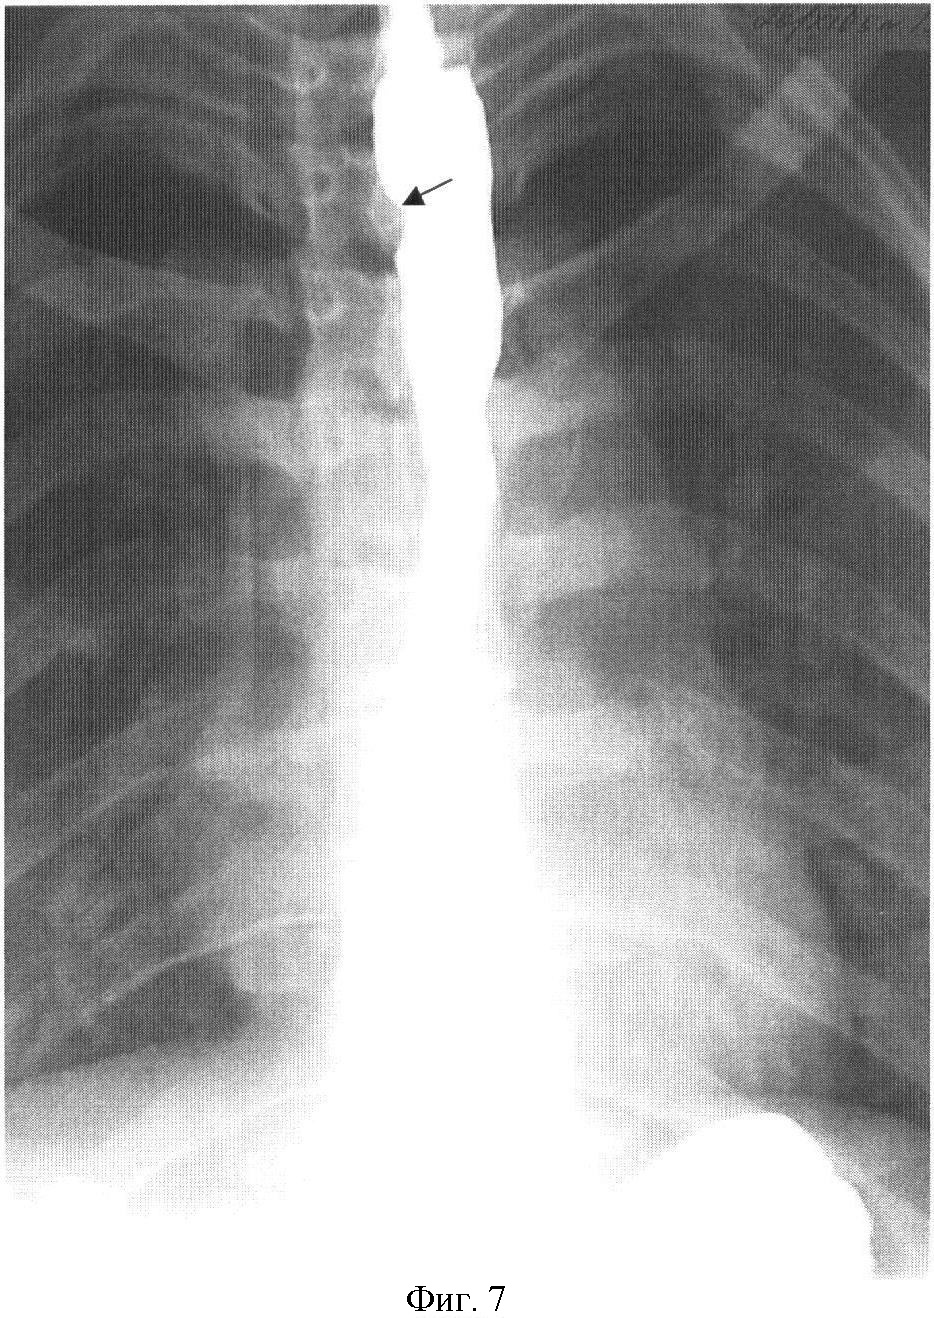

На фиг.1 представлена рентгенограмма пищевода с контрастным веществом: определяется контрастирование трахеопищеводного свища. На фиг.2 представлена эндоскопическая картина просвета пищевода: устье трахеопищеводного свища указано стрелкой. На фиг.3 представлена эндоскопическая картина просвета пищевода: предварительно в устье трахеопищеводного свища, открывающегося в просвете трахеи, было ведено 0,8 мл красящего вещества (метиленовой сини), после этого в просвете пищевода определяется прокрашивание устья трахеопищеводного свища (указано стрелкой). На фиг.4 – пломбирование устья трахеопищеводного свища тахокомбом, предварительно устье свища было последовательно подвергнуто электрокоагуляции и химиокоагуляции (96% этиловый спирт). На фиг.5 – клиппирование запломбированного устья свища. На фиг.6 – контрольная эзофагоскопия, выполненная через 3 месяца после операции: в просвете пищевода в области устья трахеопищеводного свища определяются две скрепки. На фиг.7 – контрольная рентгенограмма после эндоскопического лечения (через 3 месяца): в области трахеопищеводного свища определяется незначительный дефект наполнения (указан стрелкой), трахеопищеводный свищ не контрастируется.

На обзорной рентгенограмме органов грудной клетки в области устья трахеопищеводного свища определяются две скрепки. При рентгеноскопии с контрастным веществом поступление последнего в трахею не определяется.

На фиброэзофагоскопии в области устья трахеопищеводного свища определяется незначительная деформация просвета пищевода с умеренной конвергенцией складок, также по передней стенке определяется две скрепки.